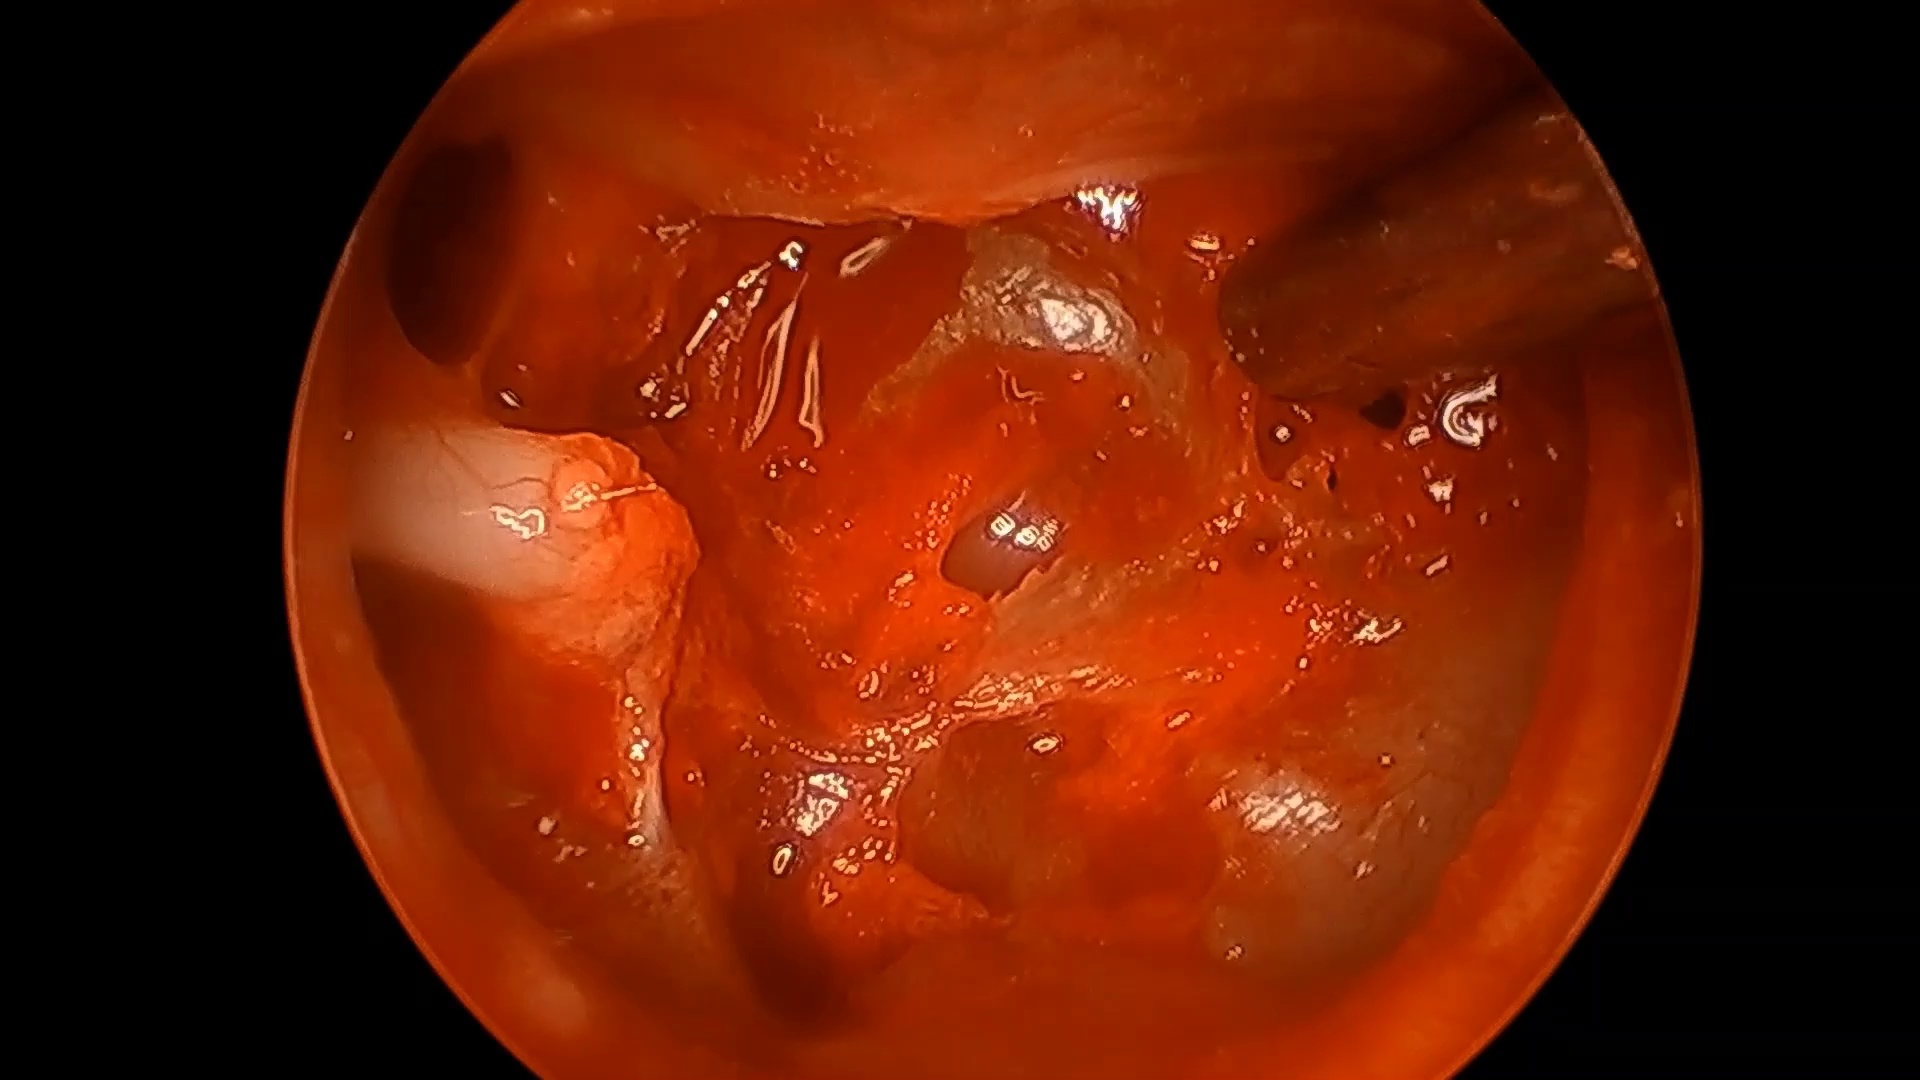

Intracapsular tonsillectomy (tonsillotomy) offers significant advantages over the extracapsular approach. By preserving residual tonsillar tissue and the capsule as a biological dressing, it protects the underlying musculature with its vessels and nerves, while delivering equivalent clinical outcomes with reduced complications of postoperative pain, dehydration, and bleeding. There is no standardized approach in performance of a tonsillotomy , unlike the extracapsular approach. Additionally, when performing a tonsillotomy on large hypertrophied tonsils, visualizing the posterior pillar—often hidden behind tonsillar tissue—can be challenging, potentially putting this muscular structure at risk for damage and negating the advantages of a tonsillotomy. We describe a standardized technique for tonsillotomy using a midline split within the tonsillar tissue, creating a “coffee bean” appearance that serves as a pivot point for retraction. This approach allows for more accurate distinction between the posterior tonsil and the pillar, resulting in more precise ablation.